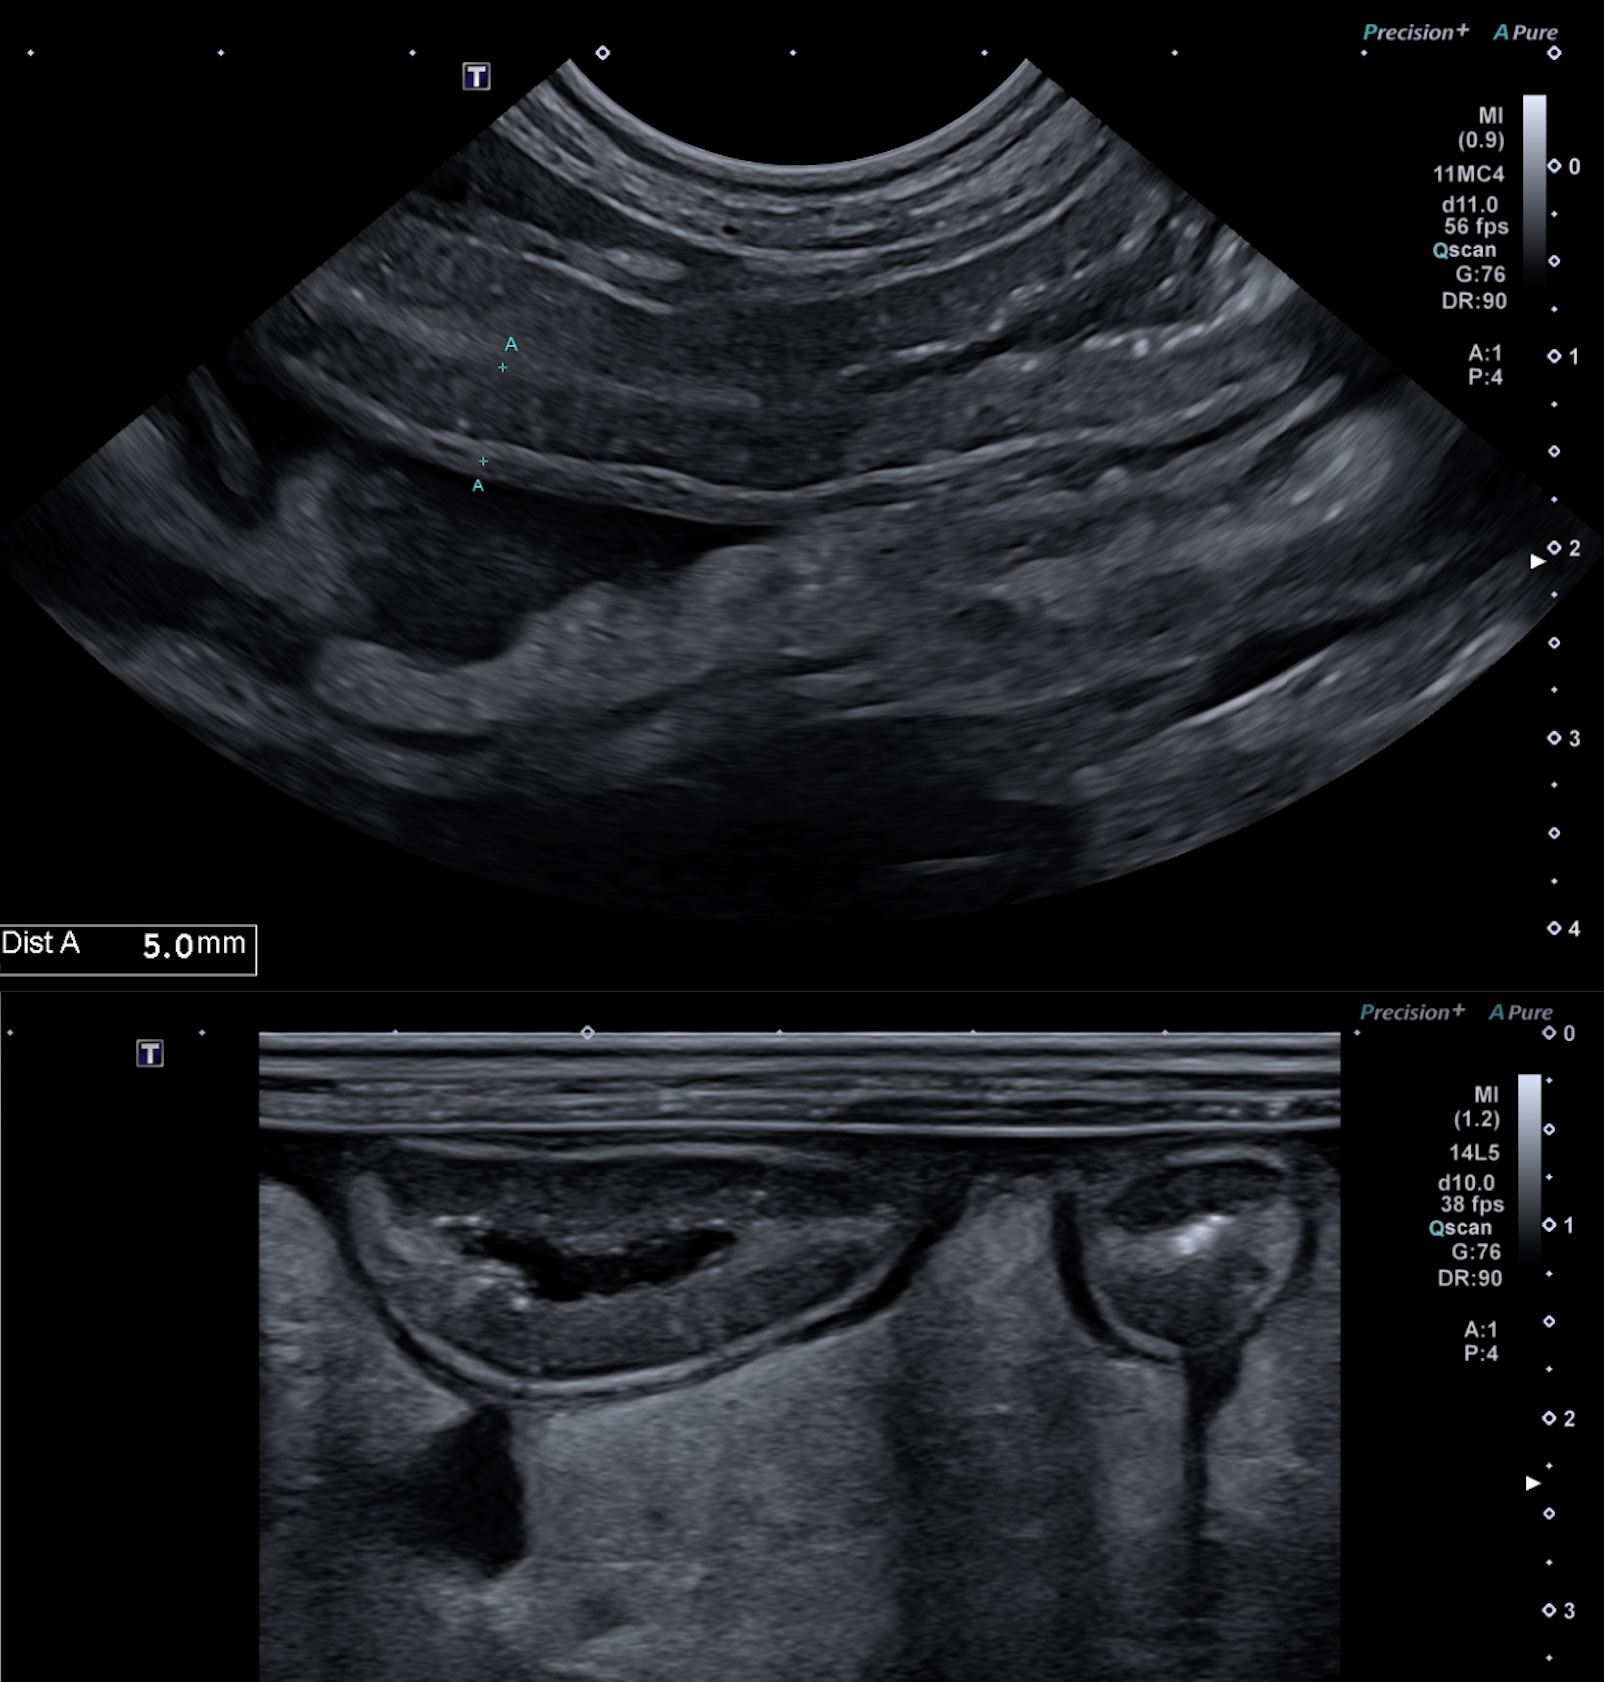

Figure 1 : lésions échographiques lors de lymphangiectasie chez un pinscher de 9 ans. Noter l'épaississement pariétal à 5 mm d'une anse jéjunale, la présence de striations et de mouchetures hyperéchogènes dans la couche muqueuse.

Les lésions muqueuses hyperéchogènes sont typiques d'entéropathie avec perte de protéines chez le chien avec une sensibilité de 76% et une spécificité de 96% dans l'étude de Gaschen et al. Lors de suspicion d'entéropathie chronique chez le chien, la mesure de l'épaisseur seule de l'intestin n'est ni sensible ni spécifique de la présence d'une entéropathie (nombreux faux négatifs). Il convient alors d'apprécier l'aspect de la muqueuse, qui peut présenter soit des "speckles" (= "mouchetures", signe non spécifique ne permettant pas de distinguer le type d'entéropathie), soit des stries hyperéchogènes - figure 1 ci dessous - (corrélé à l'histologie avec une dilatation des glandes lactéales chez le chien, d'après l'étude de Sutherland-Smith et al). Les lymphangiectasies intestinales primitives (ou maladie de Waldmann en médecine humaine), sont caractérisées par des dilatations lymphatiques digestives. Elles entrainent une fuite lymphatique (chyle) dans la lumière intestinale responsable d’une gastro-entéropathie exsudative avec hypoalbuminémie notamment.